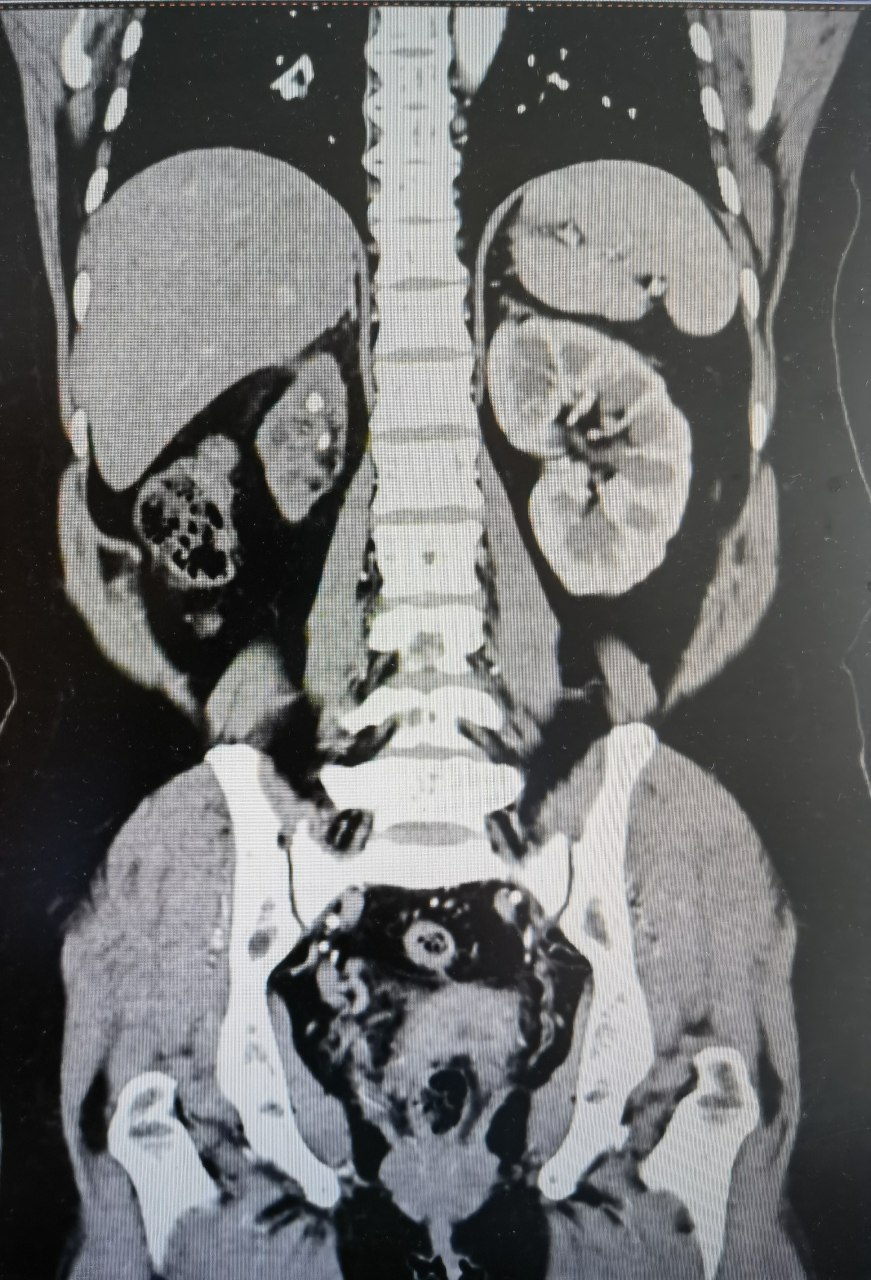

结石致重度肾积水 - 好大夫在线

ct示:右肾积水